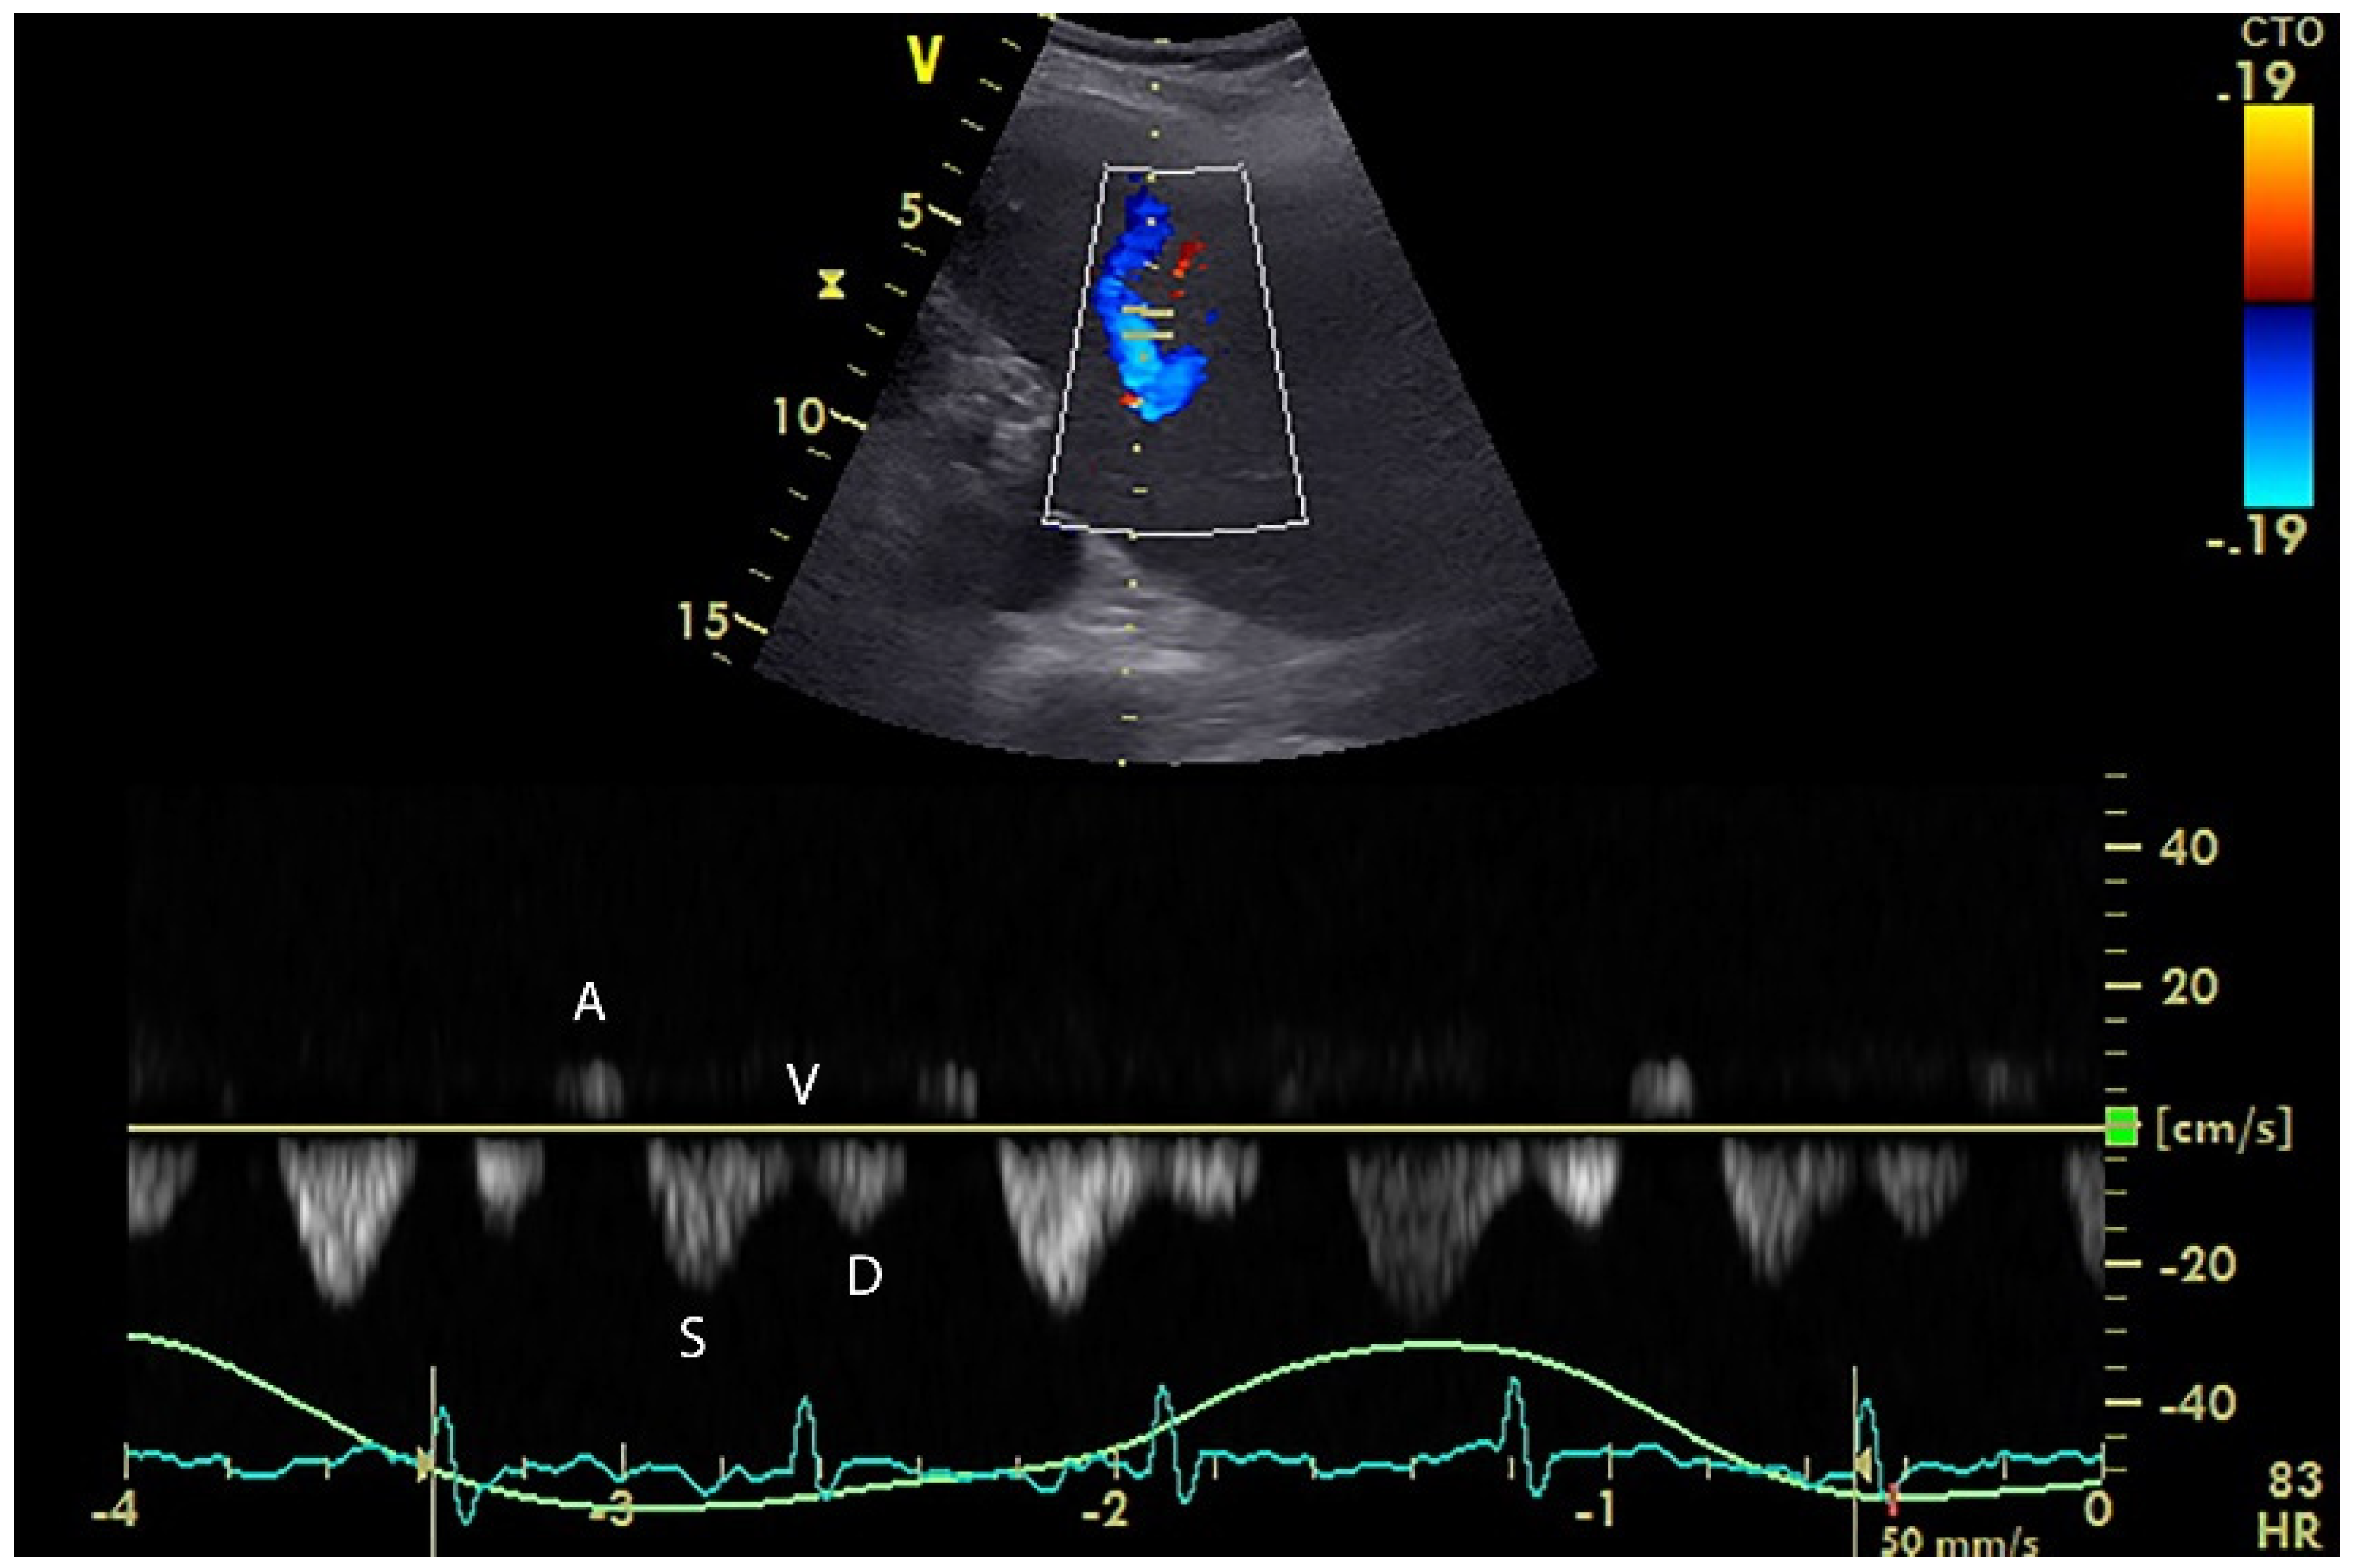

5. Hepatic Venous Flow